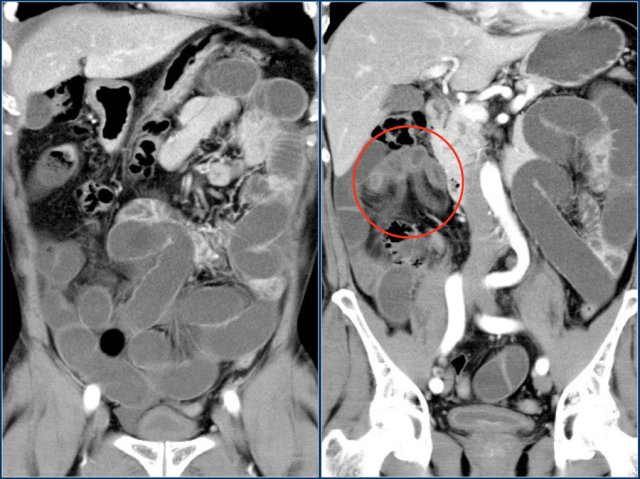

The coronal reconstruction nicely shows bowel wall enhancement in a patient with ileus due to a small bowel obstruction.

Notice the cluster of thick walled loops with poor enhancement and edema of the mesentery (red circle).

This is a closed loop obstruction with strangulation. This patient needs immediate surgery.

If this patient would have been given positive oral contrast, you probably would not have notice the ischemic bowel.